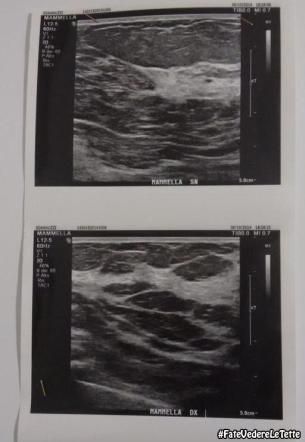

Dopo la campagna #fatevedereletette tante donne hanno scelto la prevenzione